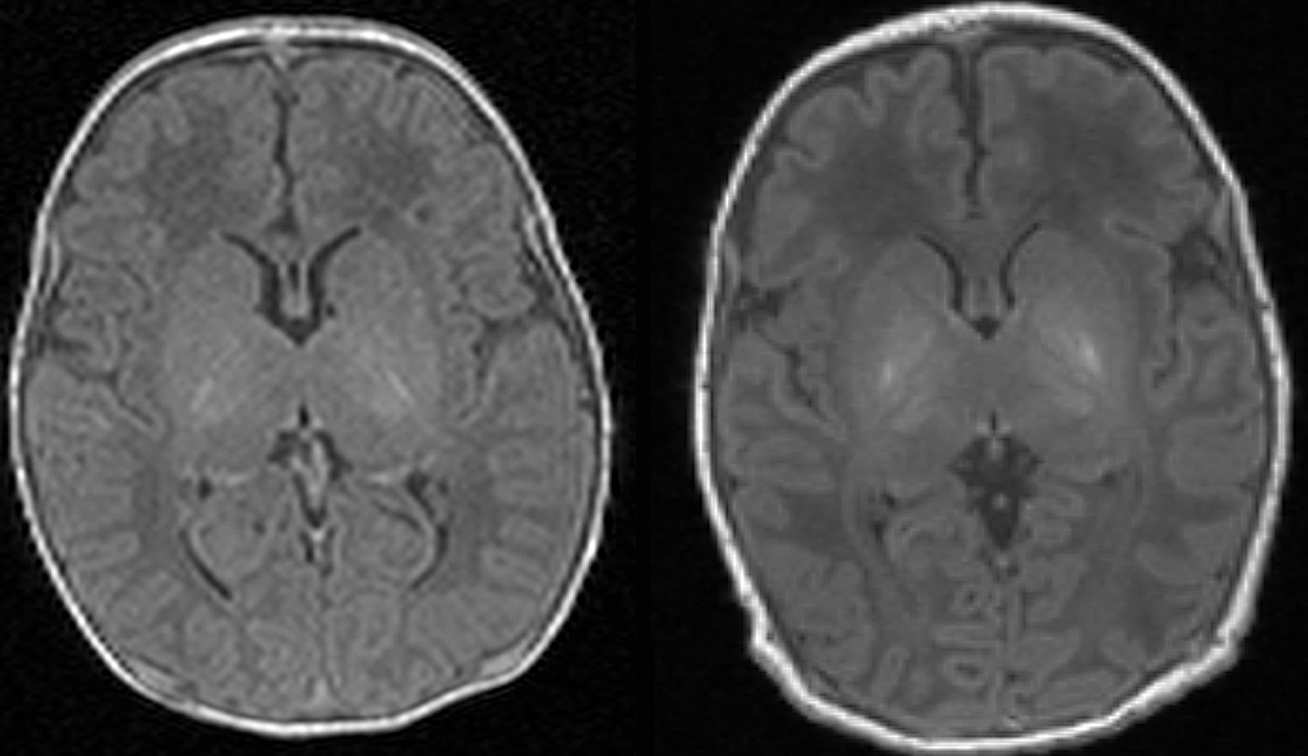

Scan one shows the brain of a healthy baby, while scan two shows that of a baby with brain damage. Compared to scan one, scan two shows abnormal brightness in the deep nuclei (in the centre of the brain), which indicates damage

Scan one (left) shows the brain of a healthy baby, while scan two (right) shows that of a baby with brain damage. Compared to scan one, scan two shows abnormal brightness in the deep nuclei (in the centre of the brain), which indicates damage